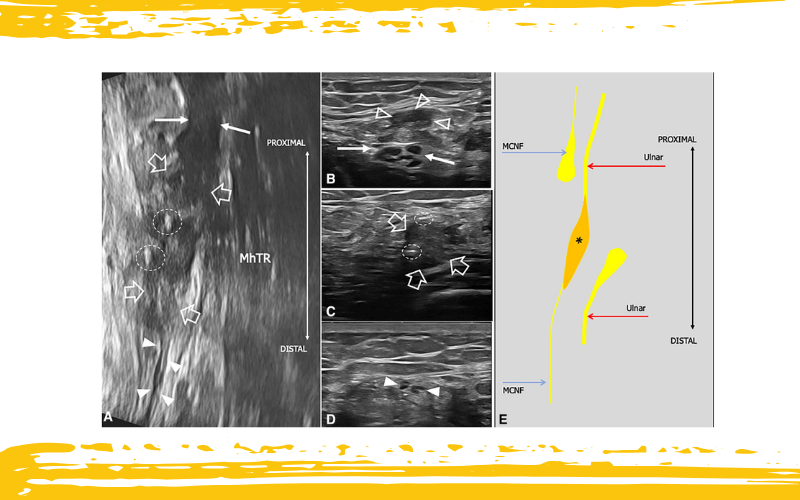

Lesión traumática del nervio cutáneo medial del antebrazo (MCNF) y del nervio cubital, con sutura accidental del muñón distal del nervio cubital al MCNF.

A. La imagen ecográfica obtenida en el tercio medio del brazo muestra un nervio cubital agrandado e hipoecoico (flechas blancas) suturado al MCNF (punta de flecha blanca). Se observa un neuroma hipertrófico e irregular (flechas delineadas) en el sitio de la sutura (elipses discontinuas).

En B, C y D, se presentan tres vistas ecográficas del MCNF y del nervio cubital, de proximal a distal.

B. El nervio cubital, con ecotextura fascicular preservada (flechas blancas), está cubierto por el muñón proximal del MCNF (cabezas de flecha delineadas).

C. Se visualiza un gran neuroma hipoecoico (flechas delineadas) con márgenes mal definidos y que contiene dos suturas metálicas (elipses discontinuas).

D. La porción distal del MCNF emerge del neuroma mostrado en el panel C.

E. Se proporciona un esquema para facilitar la comprensión de la lesión tal como se representa en la ecografía.

MhTr: cabeza medial del tríceps; *neuroma.